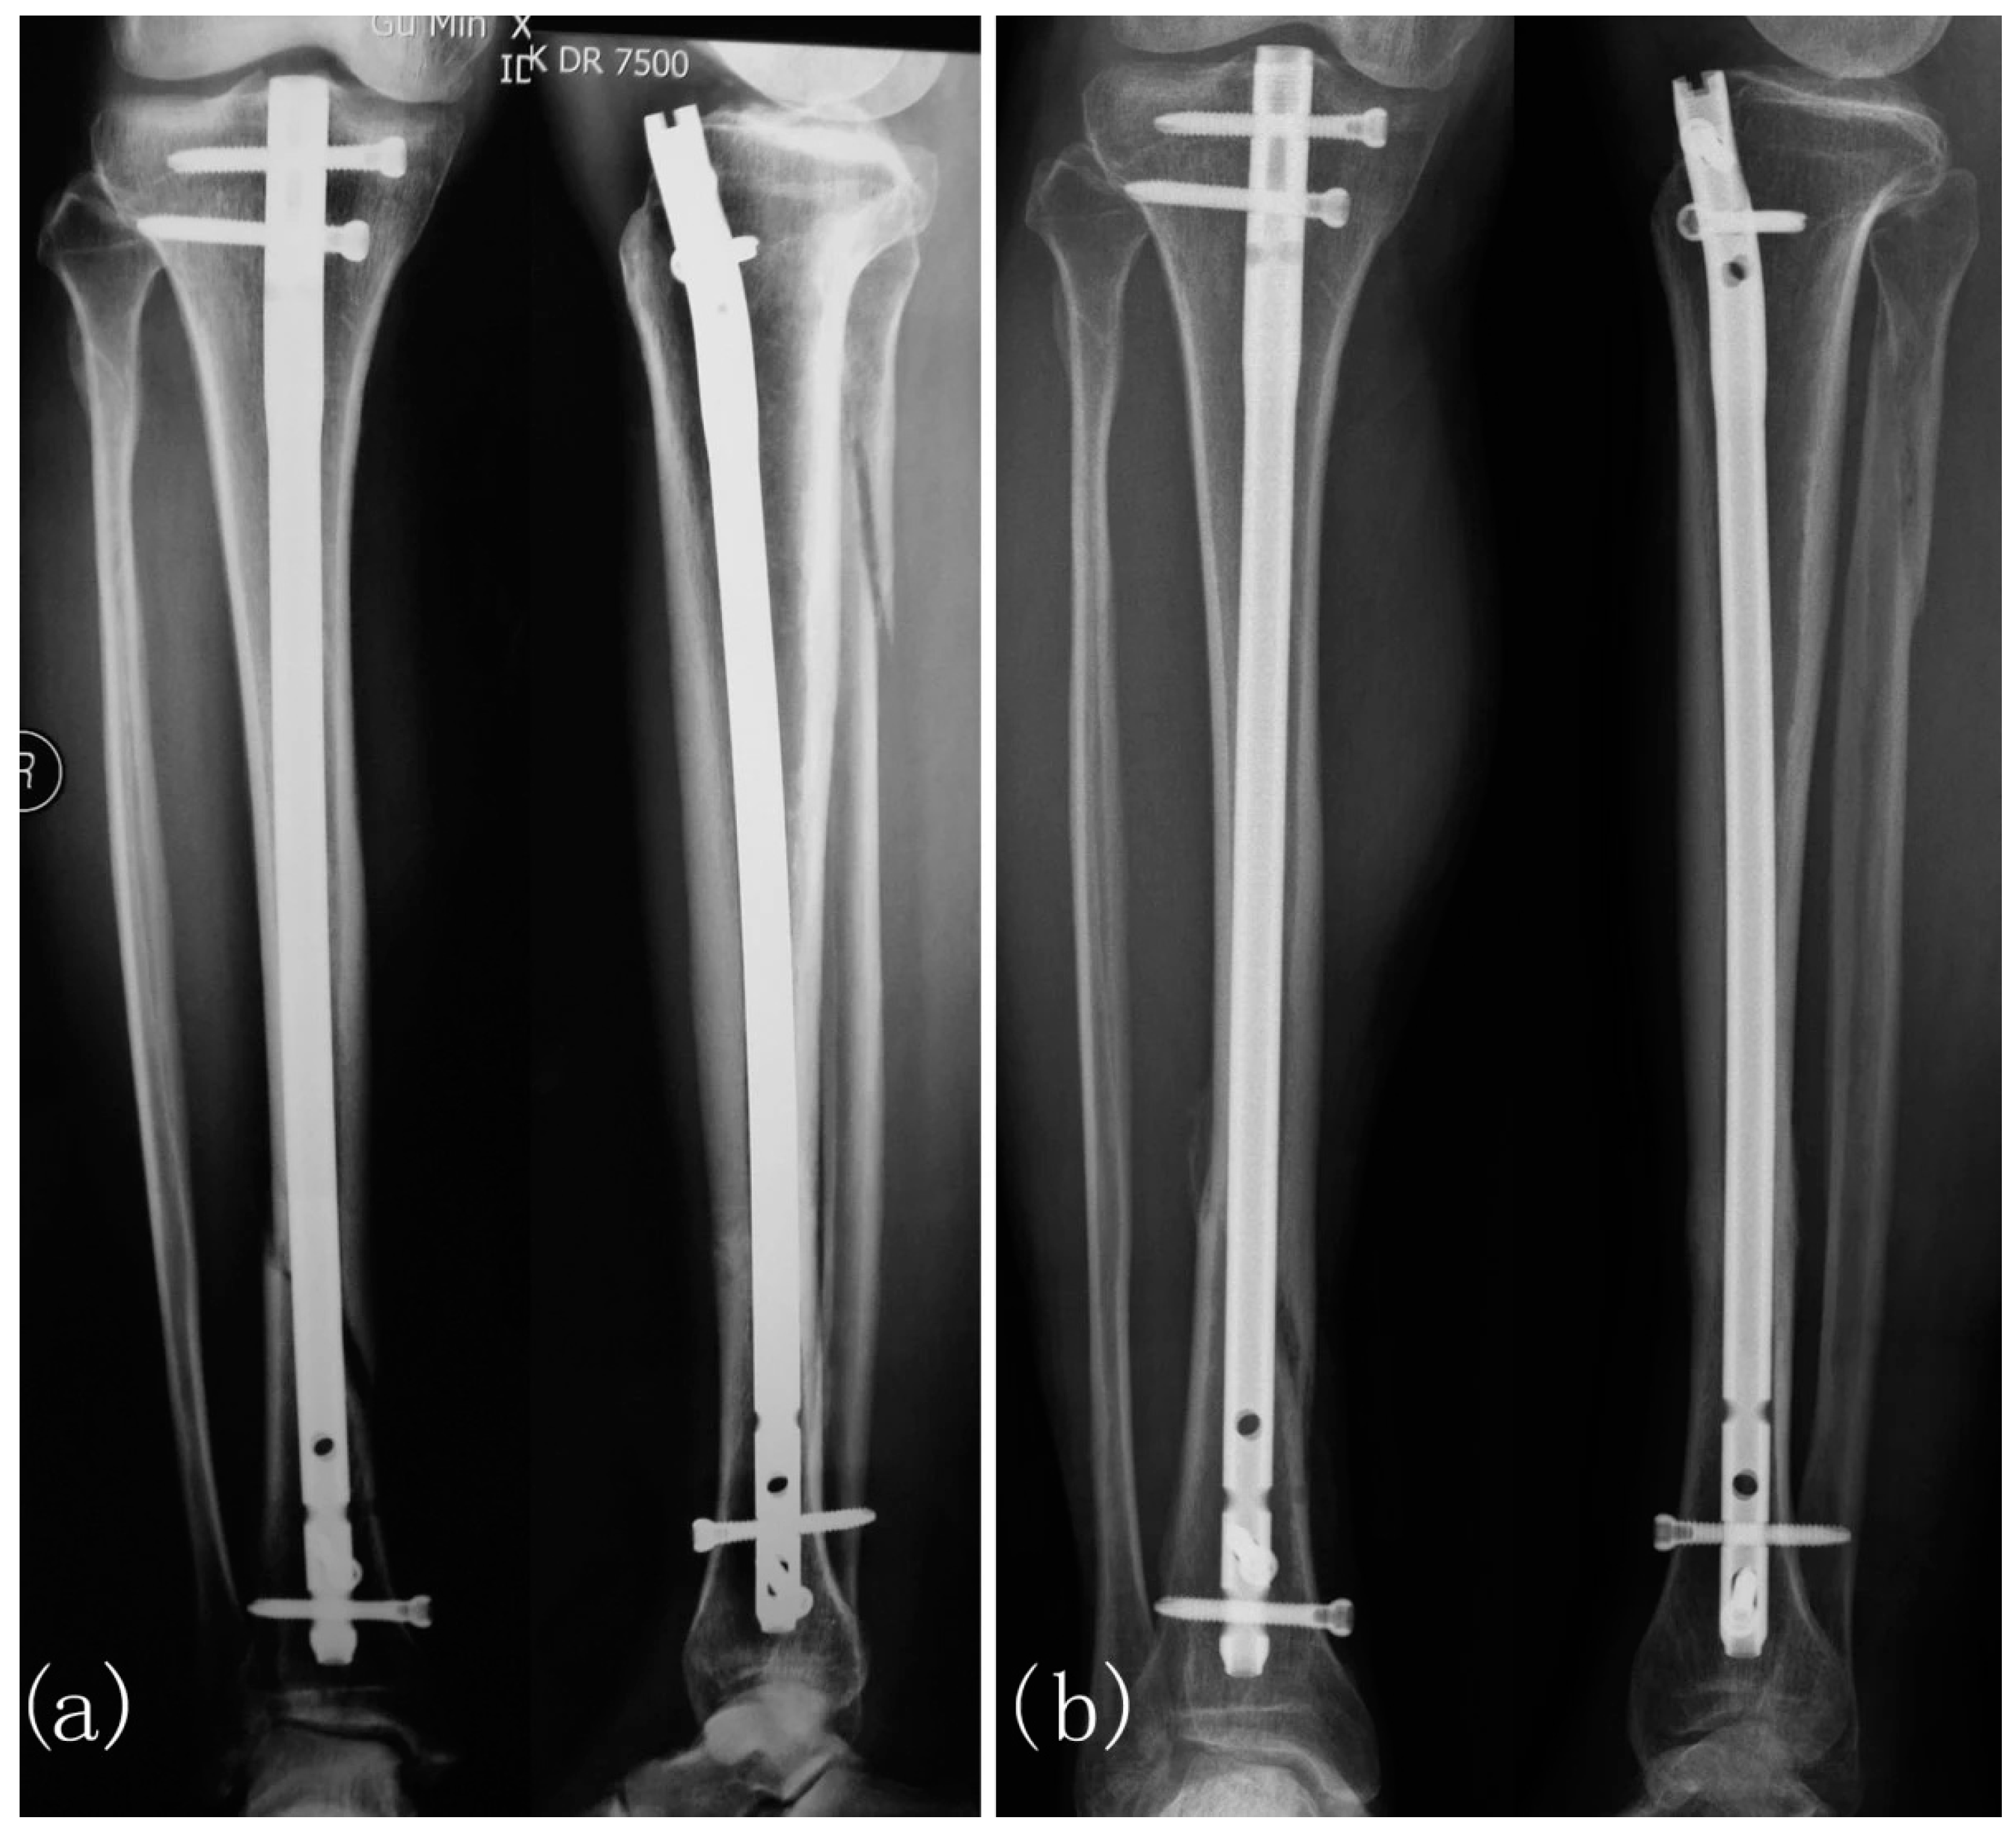

- Cebrián, J.L.; Gallego, P.; Francés, A.; Sánchez, P.; Manrique, E.; Marco, F.; López-Durán, L. Comparative study of the use of electromagnetic fields in patients with pseudoarthrosis of tibia treated by intramedullary nailing. Int. Orthop. 2010, 34, 437–440. [Google Scholar] [CrossRef] [PubMed]

- Del Buono, A.; Zampogna, B.; Osti, L.; Fontanarosa, A.; Garofalo, R.; Papalia, R. Pulsed Electromagnetic Fields after Intramedullary Nailing of Tibial Fractures: A Case Control Study. Int. Orthop. (SICOT) 2021, 45, 2945–2950. [Google Scholar] [CrossRef]